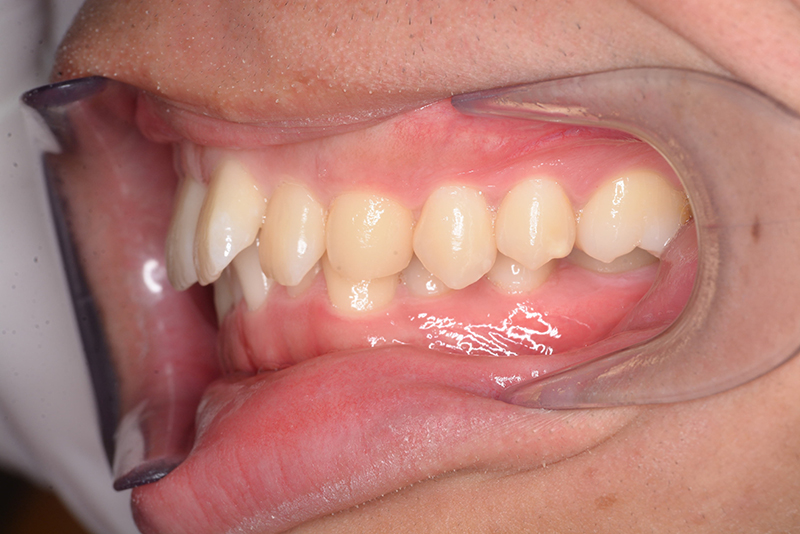

主訴 物が噛みづらい 診断名 下顎右側側切歯先天欠如を伴う過蓋咬合症例

口腔内所見 over jet 8.5mm、over bite 6.0mm、下顎前歯先天欠如、右側臼歯関係I級、左側II級(end on)、上顎歯列弓はオーボイド型なのに対して、下顎は狭窄歯列、叢生歯列弓を呈しており左側は鋏状咬合となっていた。

批評・予后 左側臼歯uprightによって鋏状咬合、過蓋咬合の改善が得られた。下顎前歯先欠によるAnterior ratio不調和と上顎前歯部叢生の改善を目的とし、上顎前歯にIPRを行ったが、治療後において左上2付近のover jetが大きく、上顎犬 歯間幅径の拡大(1.5mm)も生じているため、後戻りの懸念が残る。口元や歯列の安定性を考慮し、小臼歯抜歯も検討したがハイアングルであり下顎3-incisalのため、治療が困難となる事を危惧して非抜歯にて治療を行った。